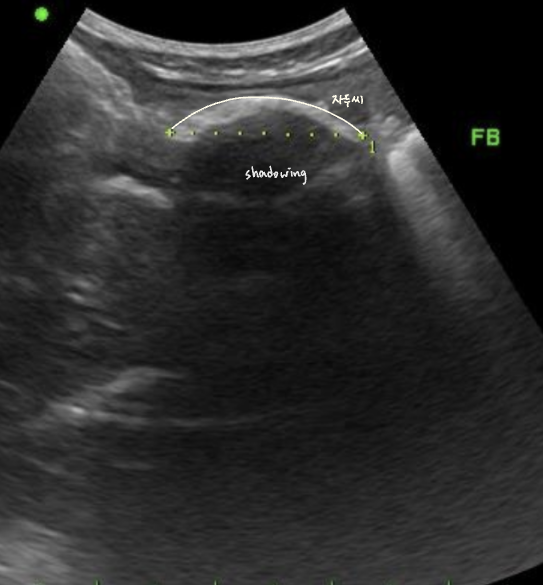

์ด๋ฌผ์ ์ด์ํ์์์ shadowing ๋ฐ์, ์์ฆ์ X-ray๋ณด๋ค ์ด์ํ๊ฐ ์ฐ์ ๋๊ธฐ๋ ํจ.

- ์์ ๊ธ์ฌ โ ์ ์์ธ์์ ์ด์ํ ๊ฒ์ฌ โ shadowing์ ๋ณด์ด๋ ์ด๋ฌผ์ ์ฆ๊ฑฐ ํ์ธ